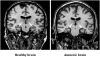

Can the experience of an emotion persist once the memory for what induced the emotion has been forgotten? We capitalized on a rare opportunity to study this question directly using a select group of patients with severe amnesia following circumscribed bilateral damage to the hippocampus. The amnesic patients underwent a sadness induction procedure (using affectively-laden film clips) to ascertain whether their experience of sadness would persist beyond their memory for the sadness-inducing films. The experiment showed that the patients continued to experience elevated levels of sadness well beyond the point in time at which they had lost factual memory for the film clips. A second experiment using a happiness induction procedure yielded similar results, suggesting that both positive and negative emotional experiences can persist independent of explicit memory for the inducing event. These findings provide direct evidence that a feeling of emotion can endure beyond the conscious recollection for the events that initially triggered the emotion.